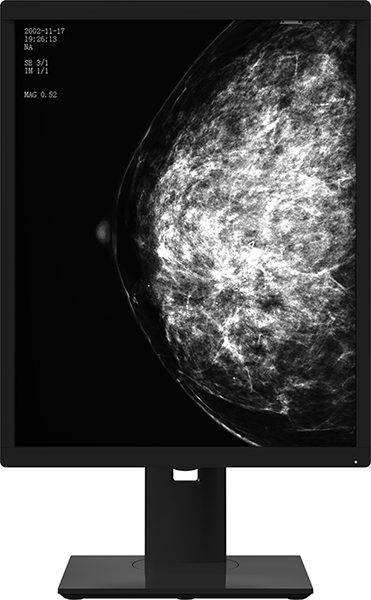

L’écran médical en niveaux de gris à 5 MP de la série 21X5M offre des performances exceptionnelles et est spécialement conçu pour les milieux médicaux. Sa résolution impressionnante en niveaux de gris, son traitement monochrome et ses performances élevées garantissent une qualité d’image précise et exacte. Cet écran est l’outil ultime pour les médecins, en leur fournissant une base de diagnostic stable et fiable qui est à la fois claire et précise.

En utilisant une mise en page non figée et en fournissant un large espace visuel, cet outil aide les médecins à obtenir le diagnostic clinique et le traitement les plus précis pour leurs patients. Il permet l’affichage simultané de diverses images d’examen, y compris des tomodensitométrie et des IRM dans un format en mosaïque, ce qui facilite la comparaison. Cette fonction permet également au personnel médical de visualiser et de comparer simultanément les nouvelles et les anciennes images numérisées, ce qui améliore considérablement l’efficacité de leur diagnostic. Le produit est principalement utilisé en conjonction avec des machines mammaires numériques, les images radiographiques résultantes étant présentées à des professionnels de la santé renommés pour servir de base au dépistage ou au diagnostic du cancer du sein.